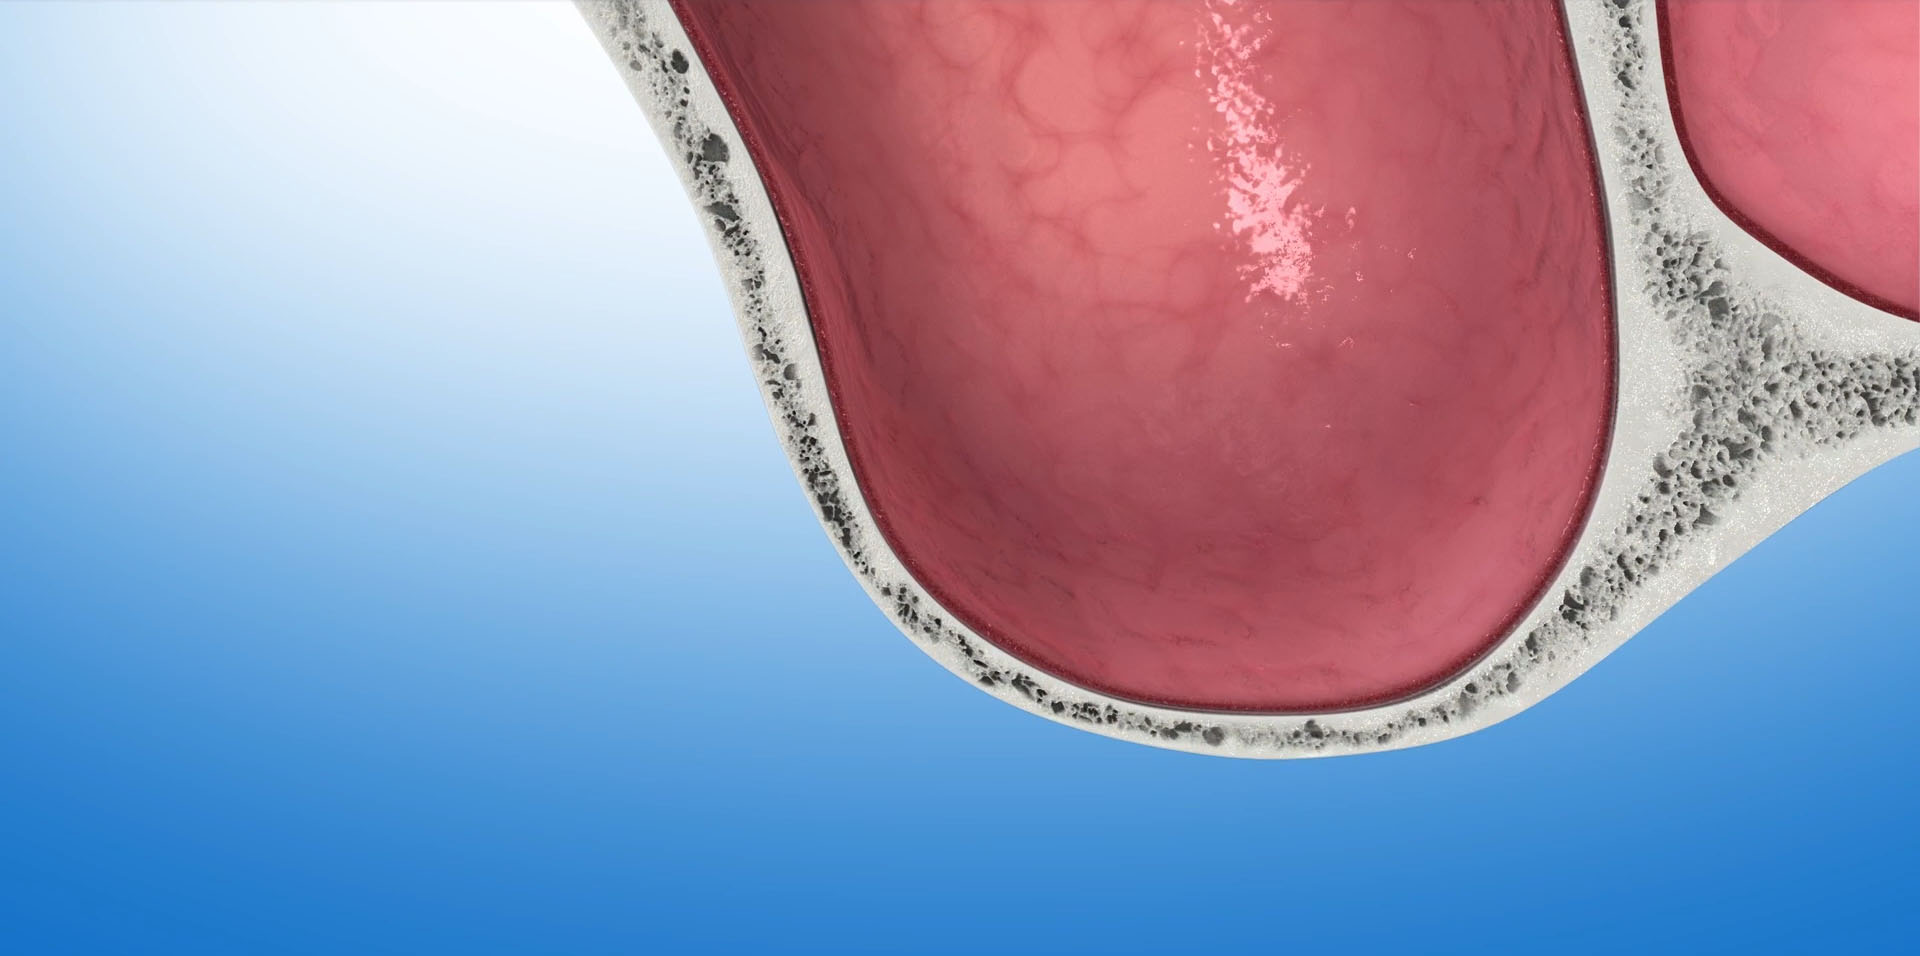

To materiał kościozastępczy produkowany z kości wołowych. W trakcie procesu produkcyjnego usuwane są z niego wszystkie składniki mogące powodować przenoszenie chorób lub wywoływać reakcje alergiczne. Naturalna struktura mineralna zostaje jednak nienaruszona. Wykazuje ona ogromne podobieństwo do struktury kości ludzkiej. Ten porowaty materiał o utkaniu ludzkiej kości stanowi doskonałe rusztowanie dla naczyń krwionośnych i komórek kościotwórczych. Stanowi matrycę, sieć dla tworzącej się tkanki kostnej. Z upływem czasu, ok.1mm w ciągu miesiąca, Bio-Oss ulega resorbcji, a miejsce po nim zajmuje nowo wytworzona kość.